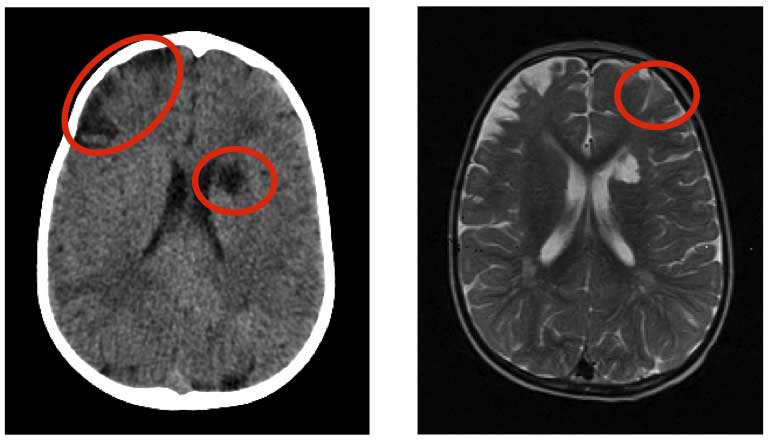

Ares, 3 anni, � arrivato in PS una domenica pomeriggio perch� dalla mattina non camminava bene. La madre raccontava che cadeva spesso quando si appoggiava sulla gamba destra e che non muoveva bene nemmeno il braccio destro. Circa 6 mesi prima aveva presentato due episodi simili a risoluzione spontanea nell�arco di 24 ore. Una settimana prima aveva avuto una virosi respiratoria. Effettivamente il bambino camminava trascinando ed extraruotando l�arto inferiore destro, mentre muoveva senza problemi gli arti superiori. Non era sofferente, la mobilizzazione della gamba destra non evocava dolore. Aveva un evidente deficit di forza all�arto inferiore destro con riflessi osteo-tendinei ipoelicitabili. Nel forte sospetto di stroke cerebrale � stata eseguita subito una TC cerebrale con mezzo di contrasto che mostrava due lesioni ipodense di tipo vascolare ischemico a carico del nucleo caudato di sinistra e del centro semiovale omolaterale, diverse lesioni pi� piccole in sede corticale e un�evidente atrofia corticale. Alla RMN le lesioni avevano un aspetto cronico-stabilizzato e non si vedevano segni di emorragia. Gli esami ematici hanno escluso un difetto della coagulazione (Figura 1).

Figura 1. Stroke cerebrale. TC (a sinistra) e RMN (a destra).